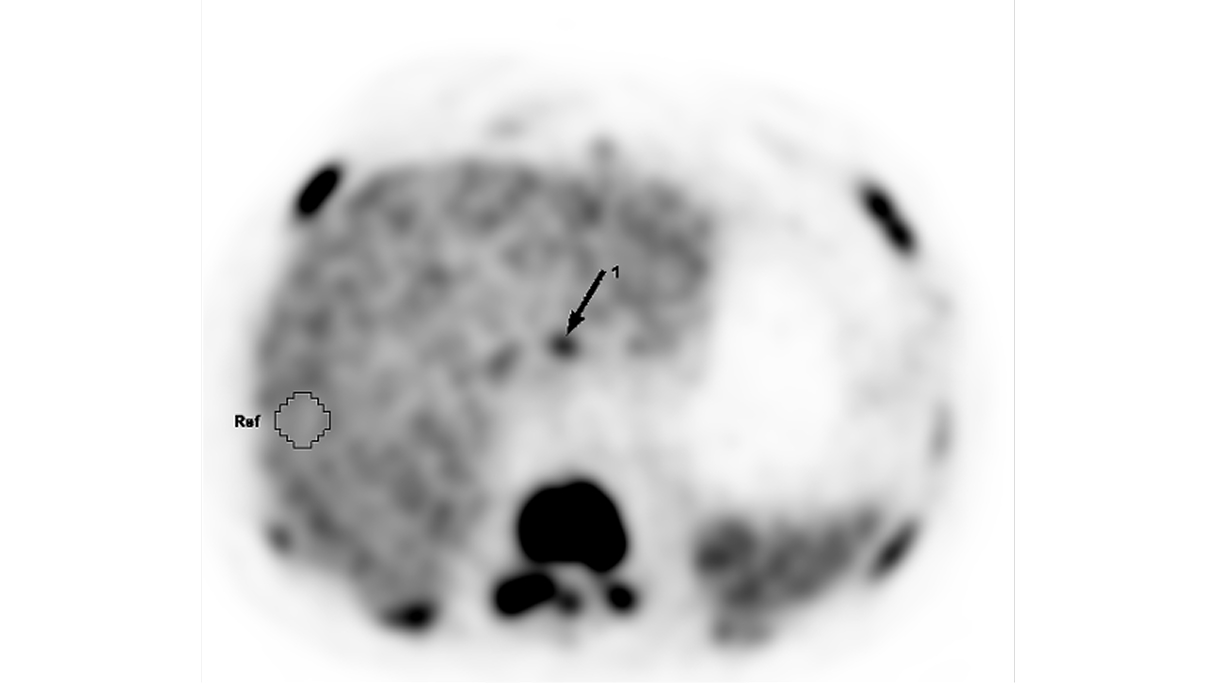

La velocità di progressione della fibrosi cardiaca: un nuovo orizzonte

La velocità di progressione della fibrosi cardiaca emerge come un nuovo e cruciale indicatore prognostico nella cardiomiopatia ipertrofica. Un recente studio evidenzia come l’LGE rate sia più predittivo degli eventi avversi rispetto alla semplice estensione della fibrosi, aprendo nuove prospettive per il monitoraggio e la gestione terapeutica dei pazienti.